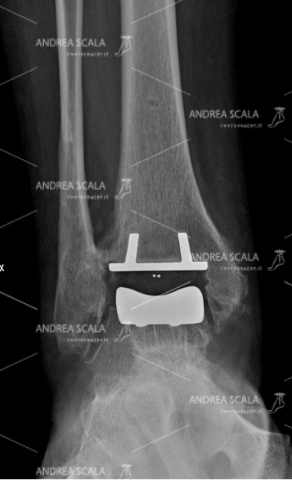

Vediamo, dunque, quali sono i vantaggi di questa operazione e perché è sempre meglio affidarsi al consiglio del dottor Scala e scegliere una protesi una misura. Le ditte che producono le protesi di caviglia hanno tutte messo a punto materiale molto perfezionati dal punto di vista della bio-compatibilità. Alcune protesi sono anallergiche, cioè si possono impiantare nei soggetti con ipersensibilità ad alcuni metalli (nickel). Altre protesi hanno l’inserto mobile, mentre altre hanno l’inserto fisso. Alcune protesi hanno il taglio dell’astragalo piatto , mentre altre hanno il taglio astragalico curvilineo. Il chirurgo deve avere una perfetta conoscenza delle caratteristiche delle protesi e degli strumenti che guidano l’impianto. Il chirurgo deve stabilire la tipologia della protesi che si adatta alle caratteristiche di ogni singolo paziente. Non è possibile mettere un solo determinato tipo di protesi che vada bene per tutti i pazienti.

Il dottor Andrea Scala opera esclusivamente utilizzando delle protesi su misura. Questo perché hanno molti vantaggi che ora vi andiamo a spiegare. In prima battuta occorre ricordare che la protesi di caviglia è composta da diversi materiali come l’acciaio, il titanio e il polietilene. Si tratta di materiali di altissima qualità e affidabilità nel campo medico che, se presi singolarmente, possono arrivare a durare anche oltre cento anni.

Da soli però questi materiali non bastano a determinare la durata della protesi. A indicare il valore concorrono anche – e soprattutto – l’accuratezza del montaggio all’interno dell’organismo che deve essere effettuato con grande cura e precisione.

In particolare, per un corretto montaggio della protesi, occorre rispettare l’anatomia della caviglia, facendo attenzione a conservare le parti anatomiche più delicate, come l’astragalo e i legamenti, nel modo migliore per evitare l’instabilità. In secondo luogo, poi, va rispettata anche la biomeccanica della caviglia, mantenendone l’allineamento. La protesi, infatti, viene stabilizzata ad ogni passo e non subisce carichi asimmetrici.

Una volta scelta la migliore protesi su misura, il dottor Andrea Scala l’applicherà avvalendosi di strumenti di alta precisione, rimuovendo prima l’articolazione malata per poi installare con estrema cura l’impianto selezionato, rispettando la struttura degli arti, l’anatomia e la stabilità.